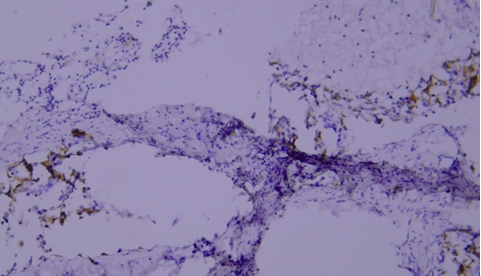

Typical Example:CD34 staining of paraffin-embedded human placental tissue sections:

HRP-directly labeled secondary antibody: Weak positive staining with low background;

Polymer enzyme-labeled secondary antibody: Strong positive staining with clean background and distinct contrast.

Conclusion: Different chromogenic systems yield distinct chromogenic results. Polymer enzyme-labeled secondary antibodies demonstrate higher sensitivity, cleaner background, and more distinct contrast compared to conventional HRP-directly labeled secondary antibodies.